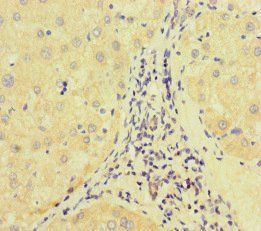

IHC staining of FFPE human bladder carcinoma with recombinant Retinoblastoma antibody (clone RB1/7080R). HIER: boil tissue sections in pH9 10 mM Tris with 1 mM EDTA for 20 min and allow to cool before testing.